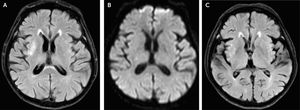

Ingresa al servicio de emergencia por un cuadro de crisis hiperglucémica que según sus exámenes de ingreso (Tabla 1), fue compatible con trastorno mixto. Recibió tratamiento según el protocolo estándar (hidratación e insulinoterapia) y 48 horas después ya presentaba criterios de remisión (Tabla 1), por lo que fue hospitalizado en el servicio de medicina interna. Setenta y dos horas después de su ingreso a emergencia, presenta movimientos compatibles con hemicorea-hemibalismo en su hemicuerpo izquierdo, por lo que se le indica una resonancia magnética cerebral (RM). En secuencia de recuperación de inversión atenuada de fluido (FLAIR) se evidencia una lesión hiperintensa interpretada como isquémica, pero sin representación en las secuencias de difusión ni en el mapa de coeficiente de difusión aparente (ADC), llevando a que la lesión fuese reinterpretada como un edema focalizado y no a una isquemia. En apoyo de esto, la lesión no aparece evidente en el control realizado dos meses después. (Fig. 1).

Imagen de resonancia magnética. A: Secuencia FLAIR en fase aguda mostrando hiperintensidad en ganglio basal derecho. B: Secuencia DWI (difusión) en fase aguda mostrando isointensidad en ganglio basal derecho descartando la presencia de infarto. C: Secuencia FLAIR, dos meses después se observa disminución de la hiperintensidad en el ganglio basal derecho.

Se le instaura tratamiento con risperidona 0,5mg cada 12 horas y se evalúa en el tiempo; a los 45 días de presentado el evento agudo el paciente ya no presentaba los movimientos involuntarios antes descritos, por lo que se le suspende el tratamiento y en una nueva RM cerebral (60 días post-evento) ya no se encuentra la lesión evidenciada en la primera imagen (Fig. 1).

En cuanto a la desaparición de la alteración en la RM se menciona que sucede entre 2 a 11 meses posteriores al cuadro agudo1,7,8; para el caso de nuestro paciente la resolución de la imagen se dió a los 2 meses.